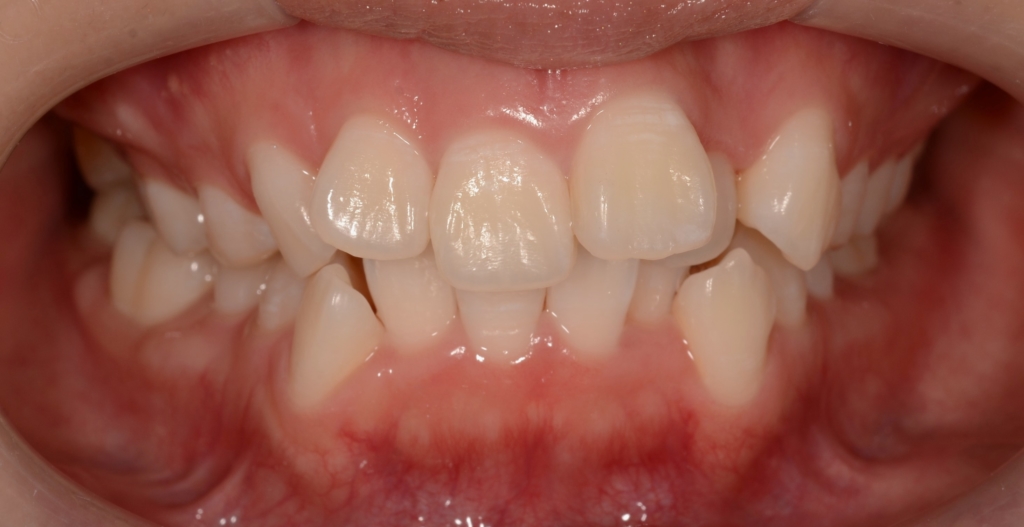

出っ歯とデコボコを治したい

患者さんは、20代の女性(社会人)です。

「出っ歯を引っ込めて、凸凹をきれいにしたい!」

口を閉じるのに力が要るので楽にしてると口唇の間から前歯が見えてしまうのと、上の前歯をもっと真っ直ぐにしたい・・・という希望もありました。

#1.(歯列の前方位による)上顎前突

#2.歯と顎の不調和による叢生(中等度)